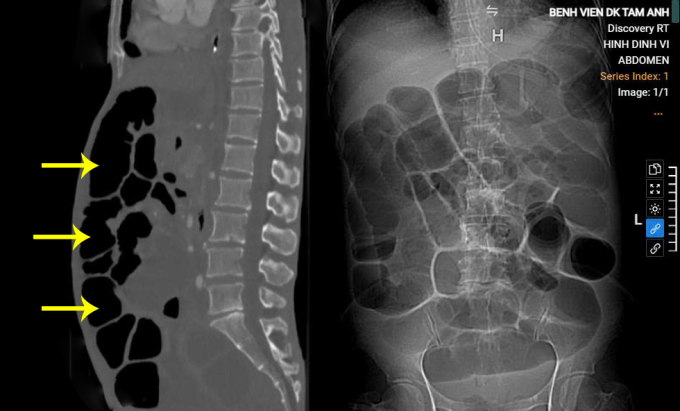

ThS.BS.CKII Lê Văn Lượng, Khoa Ngoại tổng hợp, ghi nhận bụng của bà Hằng chướng căng. Kết quả chụp CT cho thấy ung thư dạ dày đã tiến triển, mức độ di căn xâm lấn toàn bộ đại tràng gây tắc ruột, nguy cơ vỡ ruột gây viêm phúc mạc, nhiễm trùng cao. Song, bác sĩ Lượng đánh giá ruột non chưa bị di căn, có thể phẫu thuật giải quyết tắc ruột, khôi phục nuôi dưỡng qua đường tiêu hóa, nâng cao thể trạng cho người bệnh để tiếp tục điều trị.

Nội soi kiểm tra ổ bụng bệnh nhân ghi nhận nhiều dịch tự do, các quai ruột giãn căng, bác sĩ đánh giá không thể thao tác nội soi nên chuyển mổ mở. Khi phẫu thuật, bác sĩ phát hiện u hang vị dạ dày 8x10 cm, có nhiều nhân di căn xâm lấn chèn ép các tạng lân cận, các quai ruột tắc giãn, có quai giãn lớn đến 6 cm, không còn phẫu trường để tiếp cận. Do đó, êkíp chọn vị trí quai ruột phía đoạn đầu quai ruột tắc để mở lỗ, đưa ống sonde vào hút 2,5 lít dịch tiêu hóa nâu đen cùng thể tích khí lớn, nhờ vậy các quai ruột của người bệnh xẹp, giải phóng được phẫu trường. Lần lượt, bác sĩ phẫu tích các quai ruột dính vì ung thư di căn xâm lấn, mở thông hỗng tràng, đặt sonde nuôi dưỡng tiêu hóa.